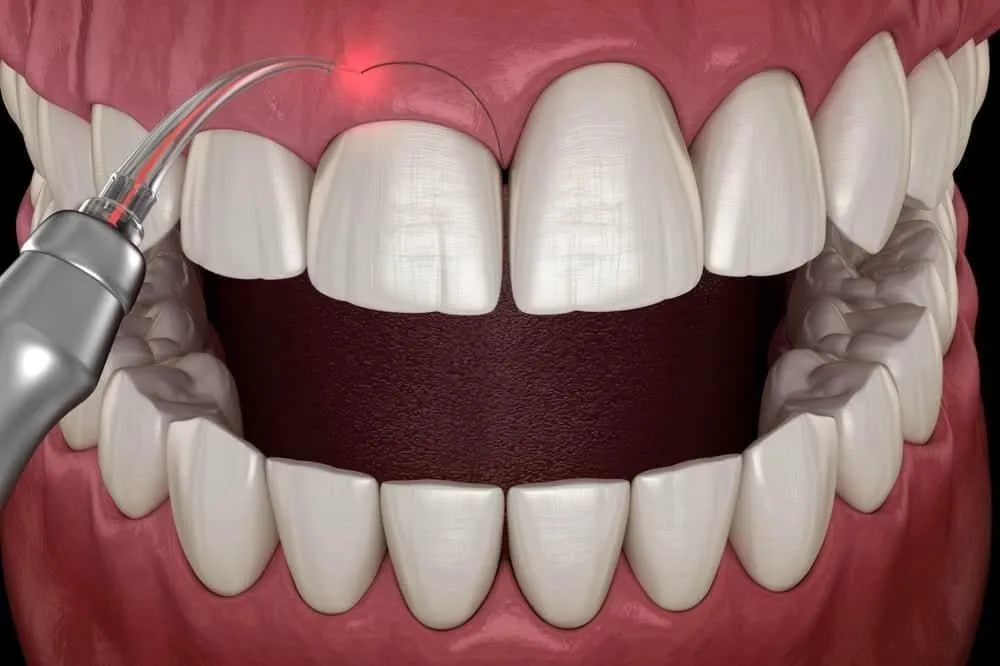

Cắt lợi là một trong những phương pháp nha khoa an toàn và hiệu quả nhất hiện nay. Phương pháp này giúp cho bạn có nụ cười

Cười hở lợi là một trong những rắc rối không ai muốn gặp phải khi nói chuyện và giao tiếp. Như tên gọi của vấn đề, người